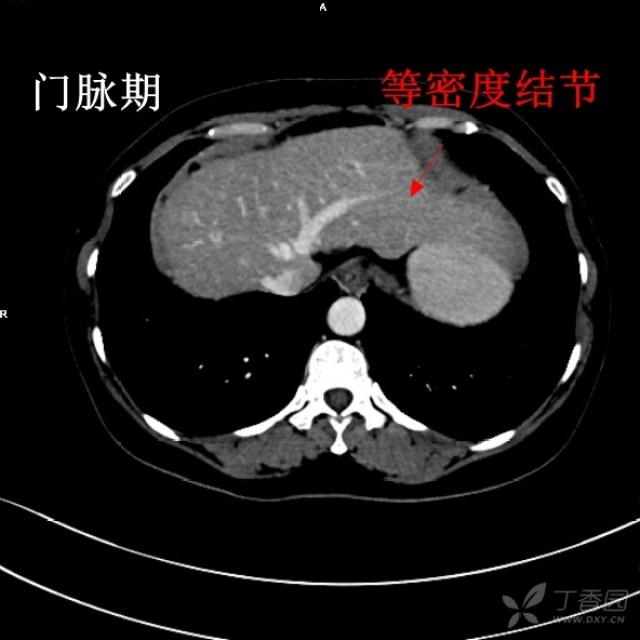

肝癌ct影像图,肝癌ct图片影像学

发现肝占位病变3月余;2 ,由于肝癌与胆囊关系密切,并有肝内转移位于ct

小肝癌

这是一个肝癌消融手术后复查的ct图像.

门诊行上腹部增强ct检查示:肝左叶,右叶多发异常强化影,考虑肝癌,afp

肝癌ct图片影像学